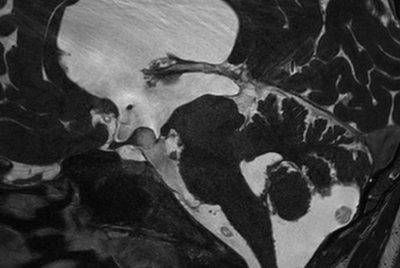

Pediatric pelvis with fistula

-